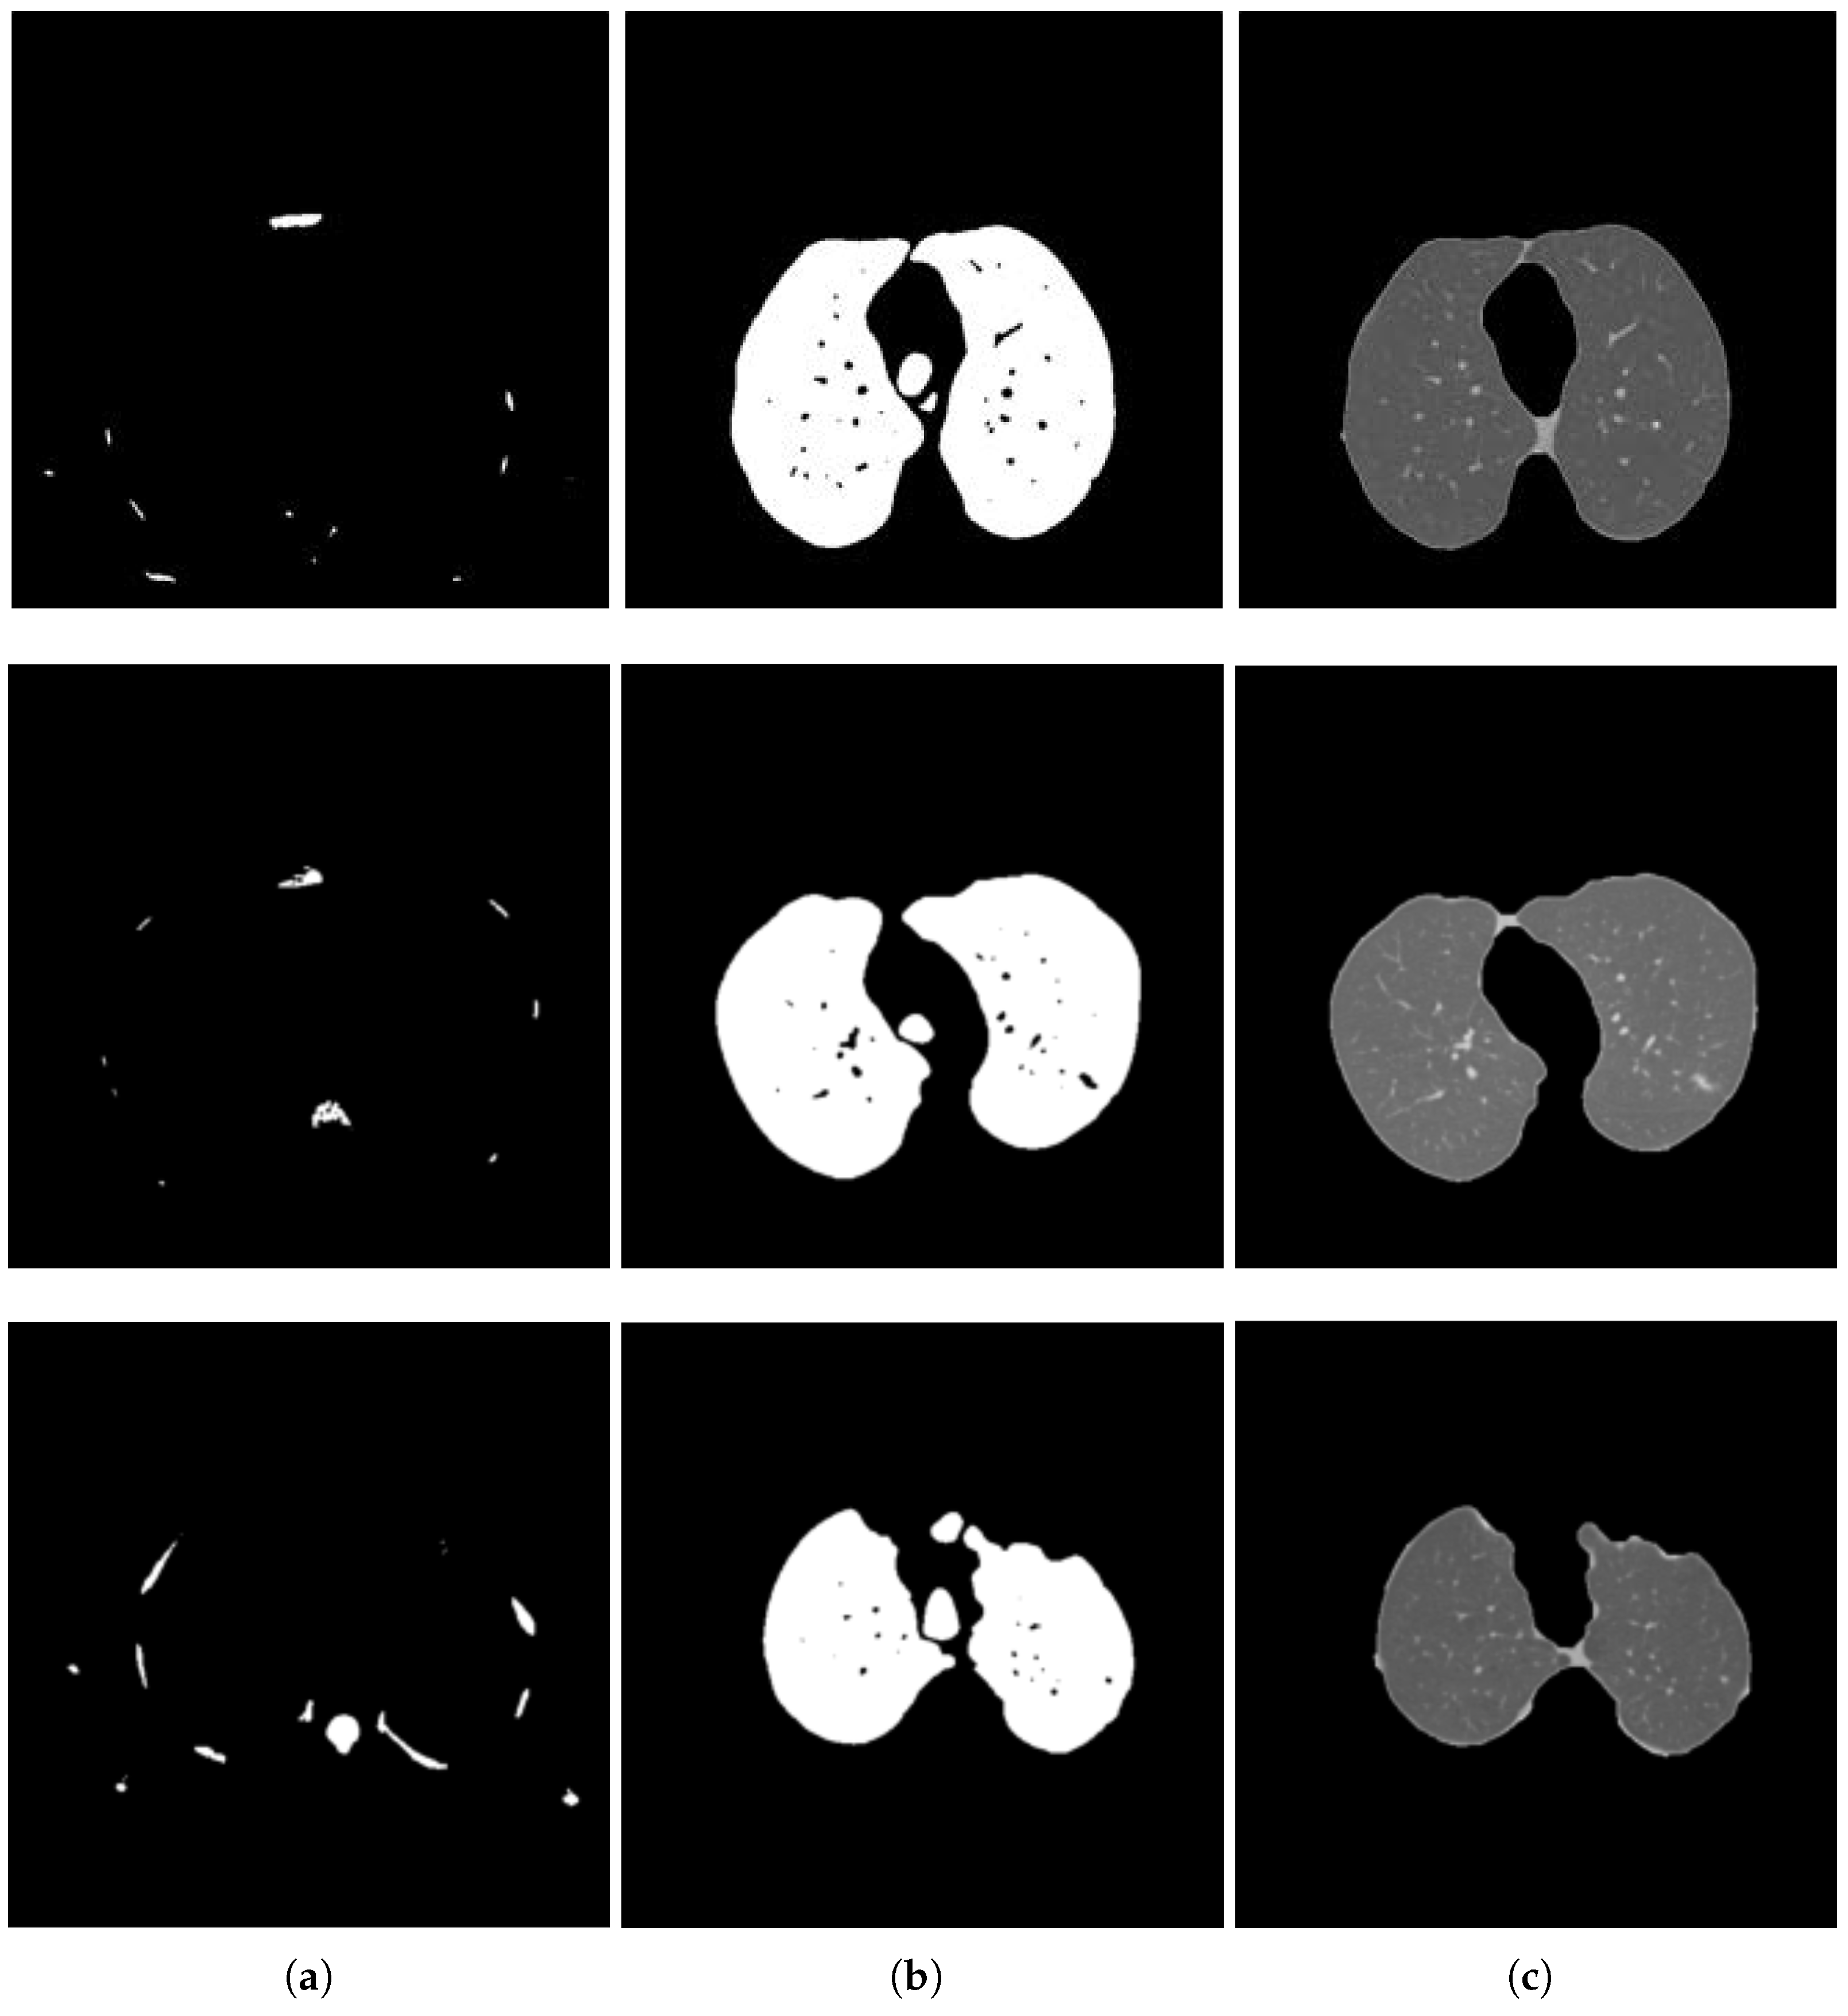

Extracting lungs from the lung window scan is indeed a tri-class pixel classification problem (Figure 1a). To achieve this pixel categorization, we use the multi-Otsu thresholding algorithm [34]. Otsu’s algorithm has been explored to solve many medical imaging problems, e.g., [35,36,37]. It finds the optimal thresholds by maximizing the between-class variance with an exhaustive search [38]. The multi-Otsu method returns two thresholds for three class problems. In our case, the first threshold comes from the valley between the first and the second peaks, and the second threshold separates the second class of pixels from the third class of pixels. The thresholds computed in the lung window shown in Figure 1a using the multi-Otsu method are shown in Figure 3 using the red markers. The second threshold separates the lungs from the rest of the image. Figure 4 shows a few lung window samples from the test dataset and the segmented lungs using the proposed method.

Figure 4.

Lung segmentation results using the proposed algorithm; in each pair, the left is the test image and the right is the segmented lung.